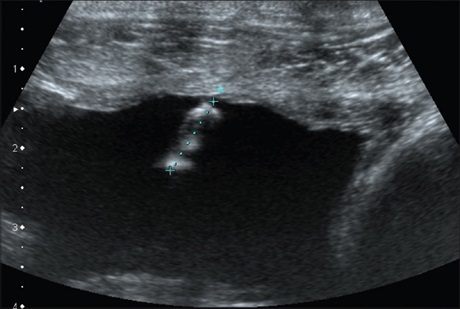

Muscle Metastasis from Prostate Cancer

We report an exceptional case of prostate cancer metastasis sites discovered on ultrasound, of the abdominal muscle, subcutaneous and liver.